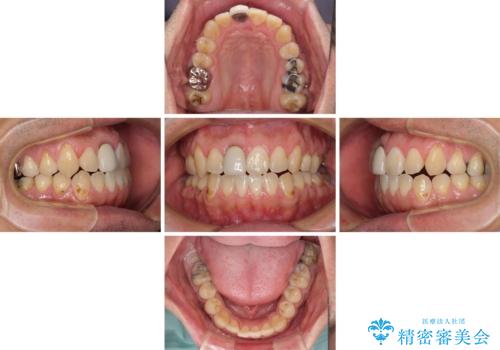

前歯のデコボコとクロスバイトをインビザライン矯正で改善

- 前歯のデコボコと上下のクロスバイトを気にして来院された患者様です。

インビザラインを用い、IPR(歯と歯の間を削る)と歯列全体を拡大させることで、歯並びを整えていくこととしました。

上の前歯が下の前歯を乗り越える際、奥歯がほとんど咬めない時期があり、乗り越えた後も、インビザライン特有の奥歯の咬みにくさが続きました。

咬み合わせ改善のために治療期間を要しましたが、最終的に奥歯はしっかりと咬めるようになりました